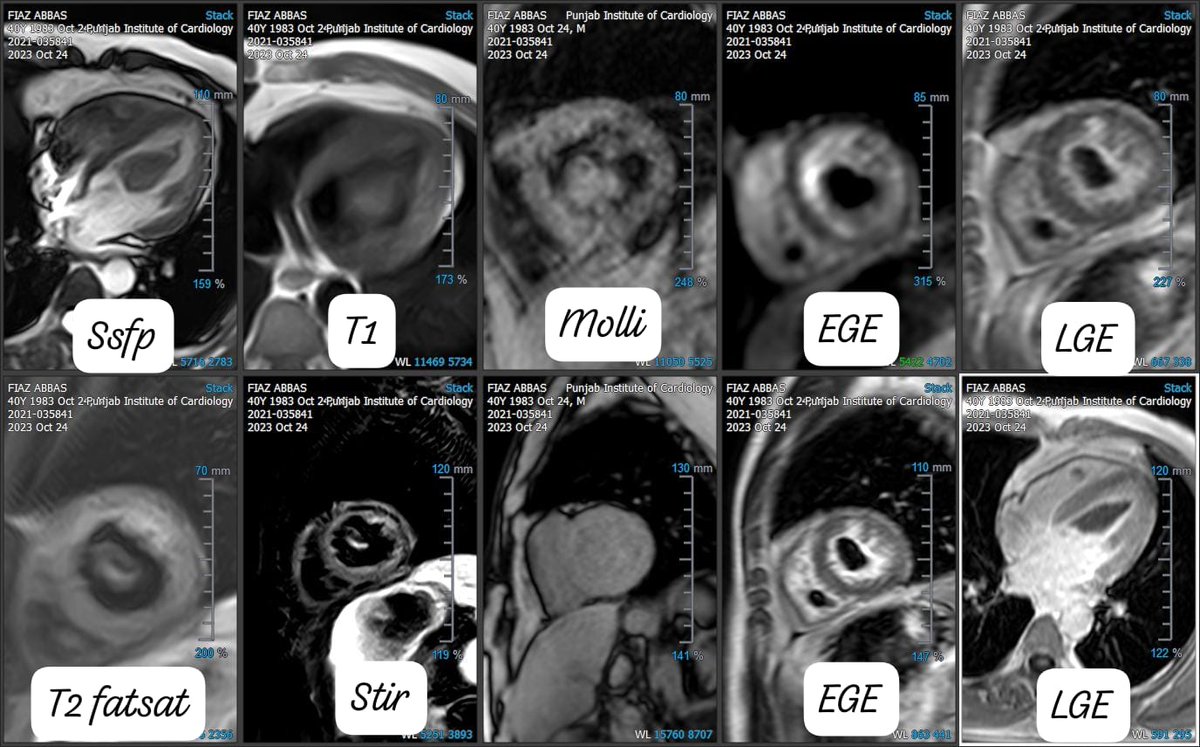

18 y girl. atrial flutter/fibrillation. ECHO: HOCM CMR: RESTRICTIVE PHYSIOLOGY, HOCM, MILD MR, SAM, BI-ATRIAL DILATION, T1 HIGH, 16 % LV LGE, LA AND LAA LGE. ATRIAL MYOPATHY. #CMR.